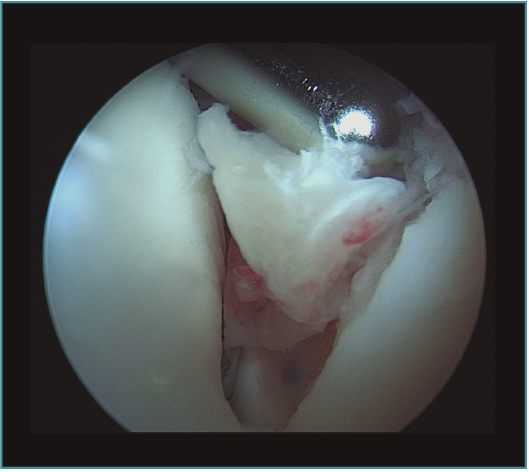

Método: hemos revisado 38 pacientes con codo rígido postraumático o degenerativo que se trataron mediante artrolisis artroscópica entre 2013 y 2016, con un seguimiento medio de 25 meses (38-15). Según la etiología de la rigidez, clasificamos a los pacientes en 2 grupos: grupo 1, los pacientes con rigidez por patología degenerativa del codo, y grupo 2, los pacientes con rigidez postraumática. Clasificamos la rigidez siguiendo la escala de Morrey y utilizamos la escala funcional Mayo Elbow Performance Index (MEPI), que evalúa el dolor, la movilidad, la estabilidad y la función del codo pre- y postoperatoriamente. Describimos los procedimientos artroscópicos realizados en cada paciente, que incluyen la sinovectomía, el desbridamiento de tejido fibroso, la capsulectomía anterior y/o posterior, la resección de osteofitos en la parte anterior y posterior del codo, la extirpación de cuerpos libres y la liberación “abierta” del nervio cubital.

Method: a review was performed on 38 patients with stiff elbow due to degenerative or post-traumatic reasons, and who were treated by arthroscopic arthrolysis between 2013 and 2016, with a mean follow-up of 25 months (38-15). Elbow stiffness was classified following the Morrey scale and the Mayo Elbow Performance Index (MEPI) functional scale was used to evaluate pain, mobility, stability and elbow function pre- and post-operatively. The arthroscopic procedures performed on each patient are described, including synovectomy, debridement of fibrous tissue, anterior and/or posterior capsulotomy, resection of osteophytes in the anterior and posterior part of the elbow, extirpation of loose bodies and open release of the ulnar nerve.